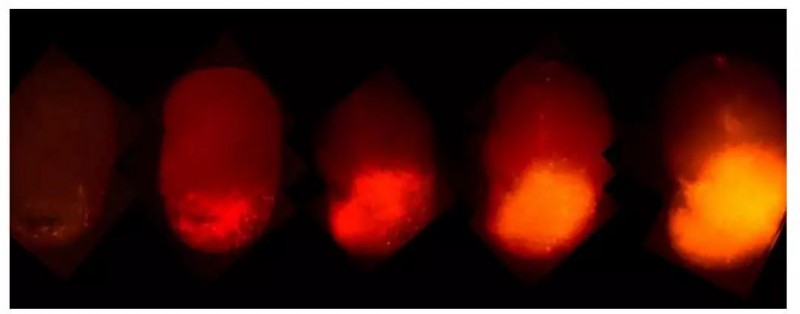

Salk实验室一直在使用干细胞在培养皿中产生这些小的(大约4mm)3D结构,并且希望通过这一模型研究GBM。使用CRISPR-Cas9工具在类器官的一些细胞中编辑与癌症紧密相关的两个基因HRas和p53。HRas是一种致癌基因,可促进细胞猖獗地生长,而p53则是一种肿瘤抑制因子,是组织癌细胞生长的。

该团队向致癌HRAS添加了一种称为tdTomato的荧光红色标记,可以追踪癌细胞的走向。此外,当类器官肿瘤被移植到小鼠的大脑中时,它们迅速生长并且类似于患者的肿瘤,这样就能获得与人同样的肿瘤组织样本,可以研究用药效果,还可以检测肿瘤侵入正常脑组织的能力。